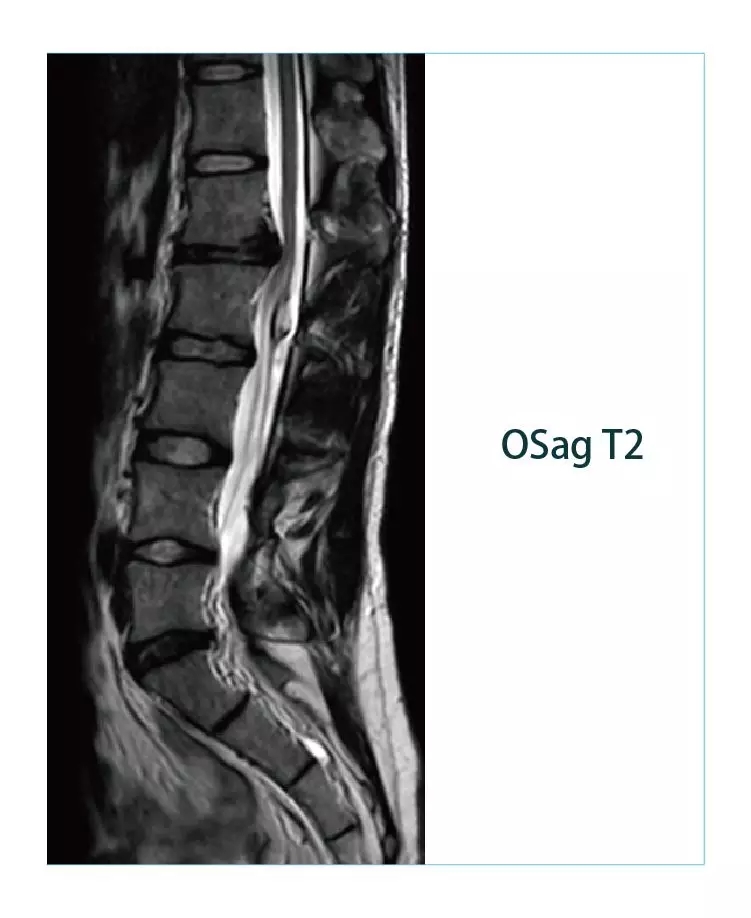

【朗润影像档案】20190329磁共振影像病例结果讨论

【朗润影像档案】磁共振影像病例分享(编号20190329)